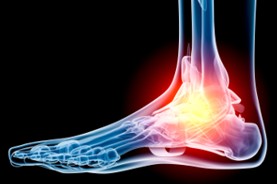

Cure for Plantar Fasciitis